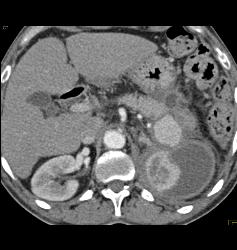

Page Kidney With Bleeding Splenic Artery Aneurysm- See Sequence